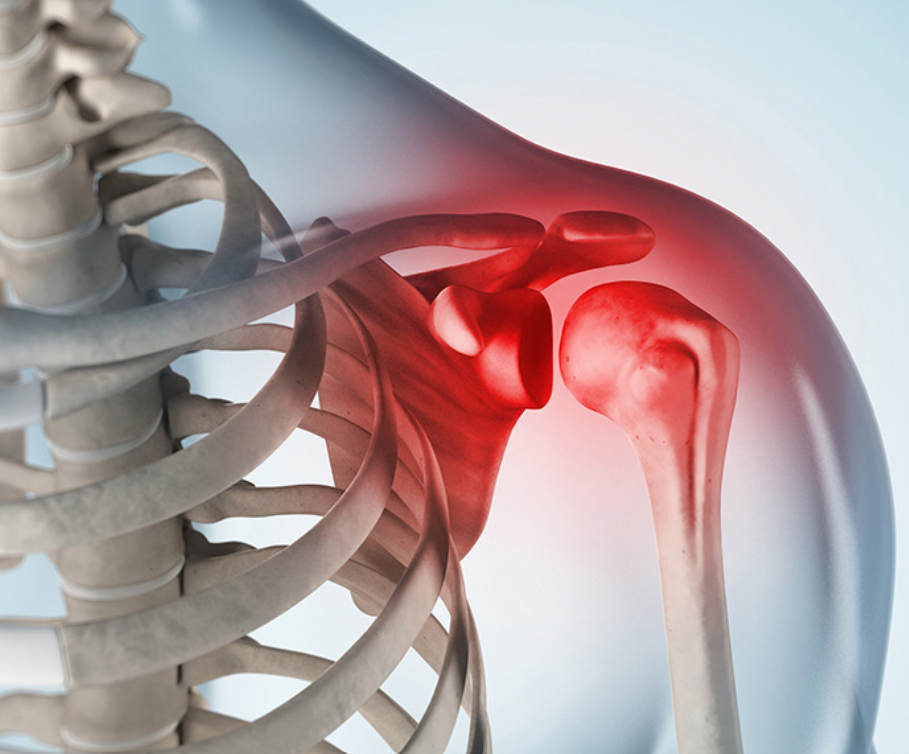

어깨통증 원인 2. 어깨 충돌증후군

어깨통증 원인 두 번째는 어깨 충돌증후군을 의심합니다. 처음에는 어깨 가동 범위에 제한이 없기 때문에 대부분 사람들은 질병을 인식하기 어렵습니다. 어깨충돌증후군은 견갑골과 견갑골을 둘러싸고 있는 상완 사이의 인대와 힘줄 또는 견갑골의 반복적인 충돌로 인해 견갑골과 주변 윤활낭에 통증과 염증을 일으키는 질환이지만 초기에는 경미하지만 지속되면 심한 통증을 일으키기 때문에 회전근개 파열의 여러 원인 중 한 가지가 될 수 있어 증상이 심해지지 않도록 해야하며 팔을 머리 위로 들어 올리거나 옷을 입거나 벗을 때, 어깨로 작업할 때 불편할 수 있는데 이런 증상이 이어지면 약물치료나 물리치료, 재활치료 등 치료를 통해 개선이 가능합니다.